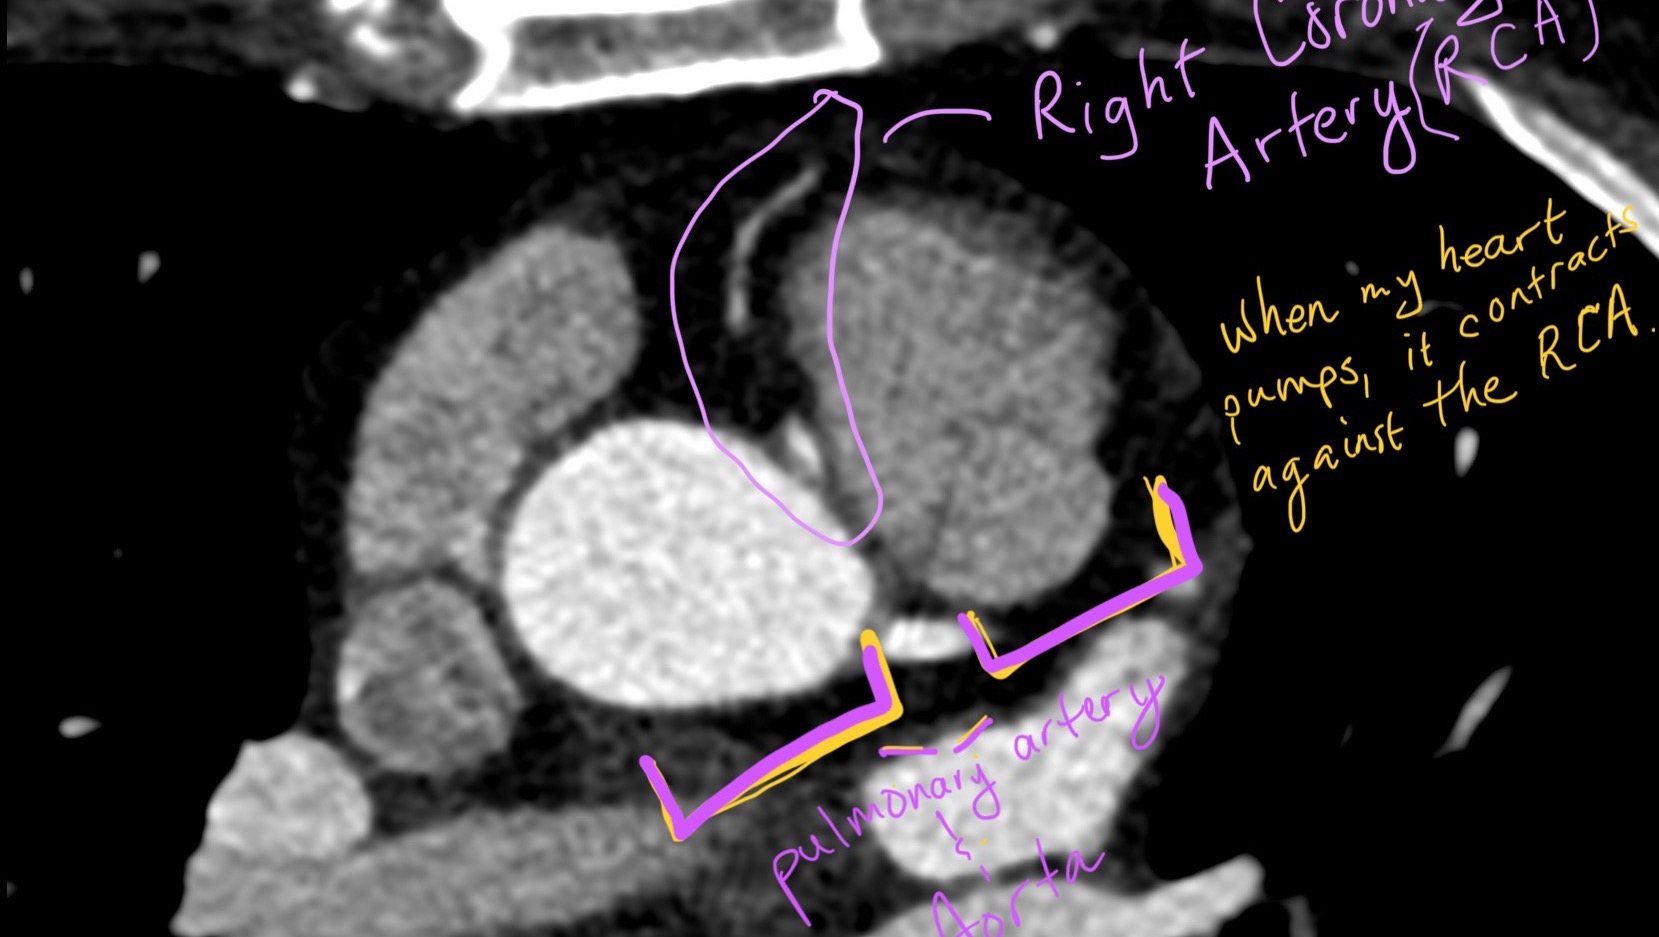

Hi! My name is Jessica and I am in need of financial support for my medical expenses and recovery, including travel expenses for cardiac rehab and follow-up appointments. I need open-heart surgery to repair a congenital defect in my heart. In this case, it means I was born with an artery in my heart that grows out of the wrong spot. It’s called anomalous origin of the right coronary artery.

The surgery procedure is called “unroofing” and it opens up the arterial wall (basically) so blood can flow through my heart.

If I don’t get the surgery, I could suffer sudden cardiac death due to pressure on the artery. One of the worst parts about this condition is that I can’t exert myself, which means no activity that’s more strenuous than a walk (and often that’s difficult!).